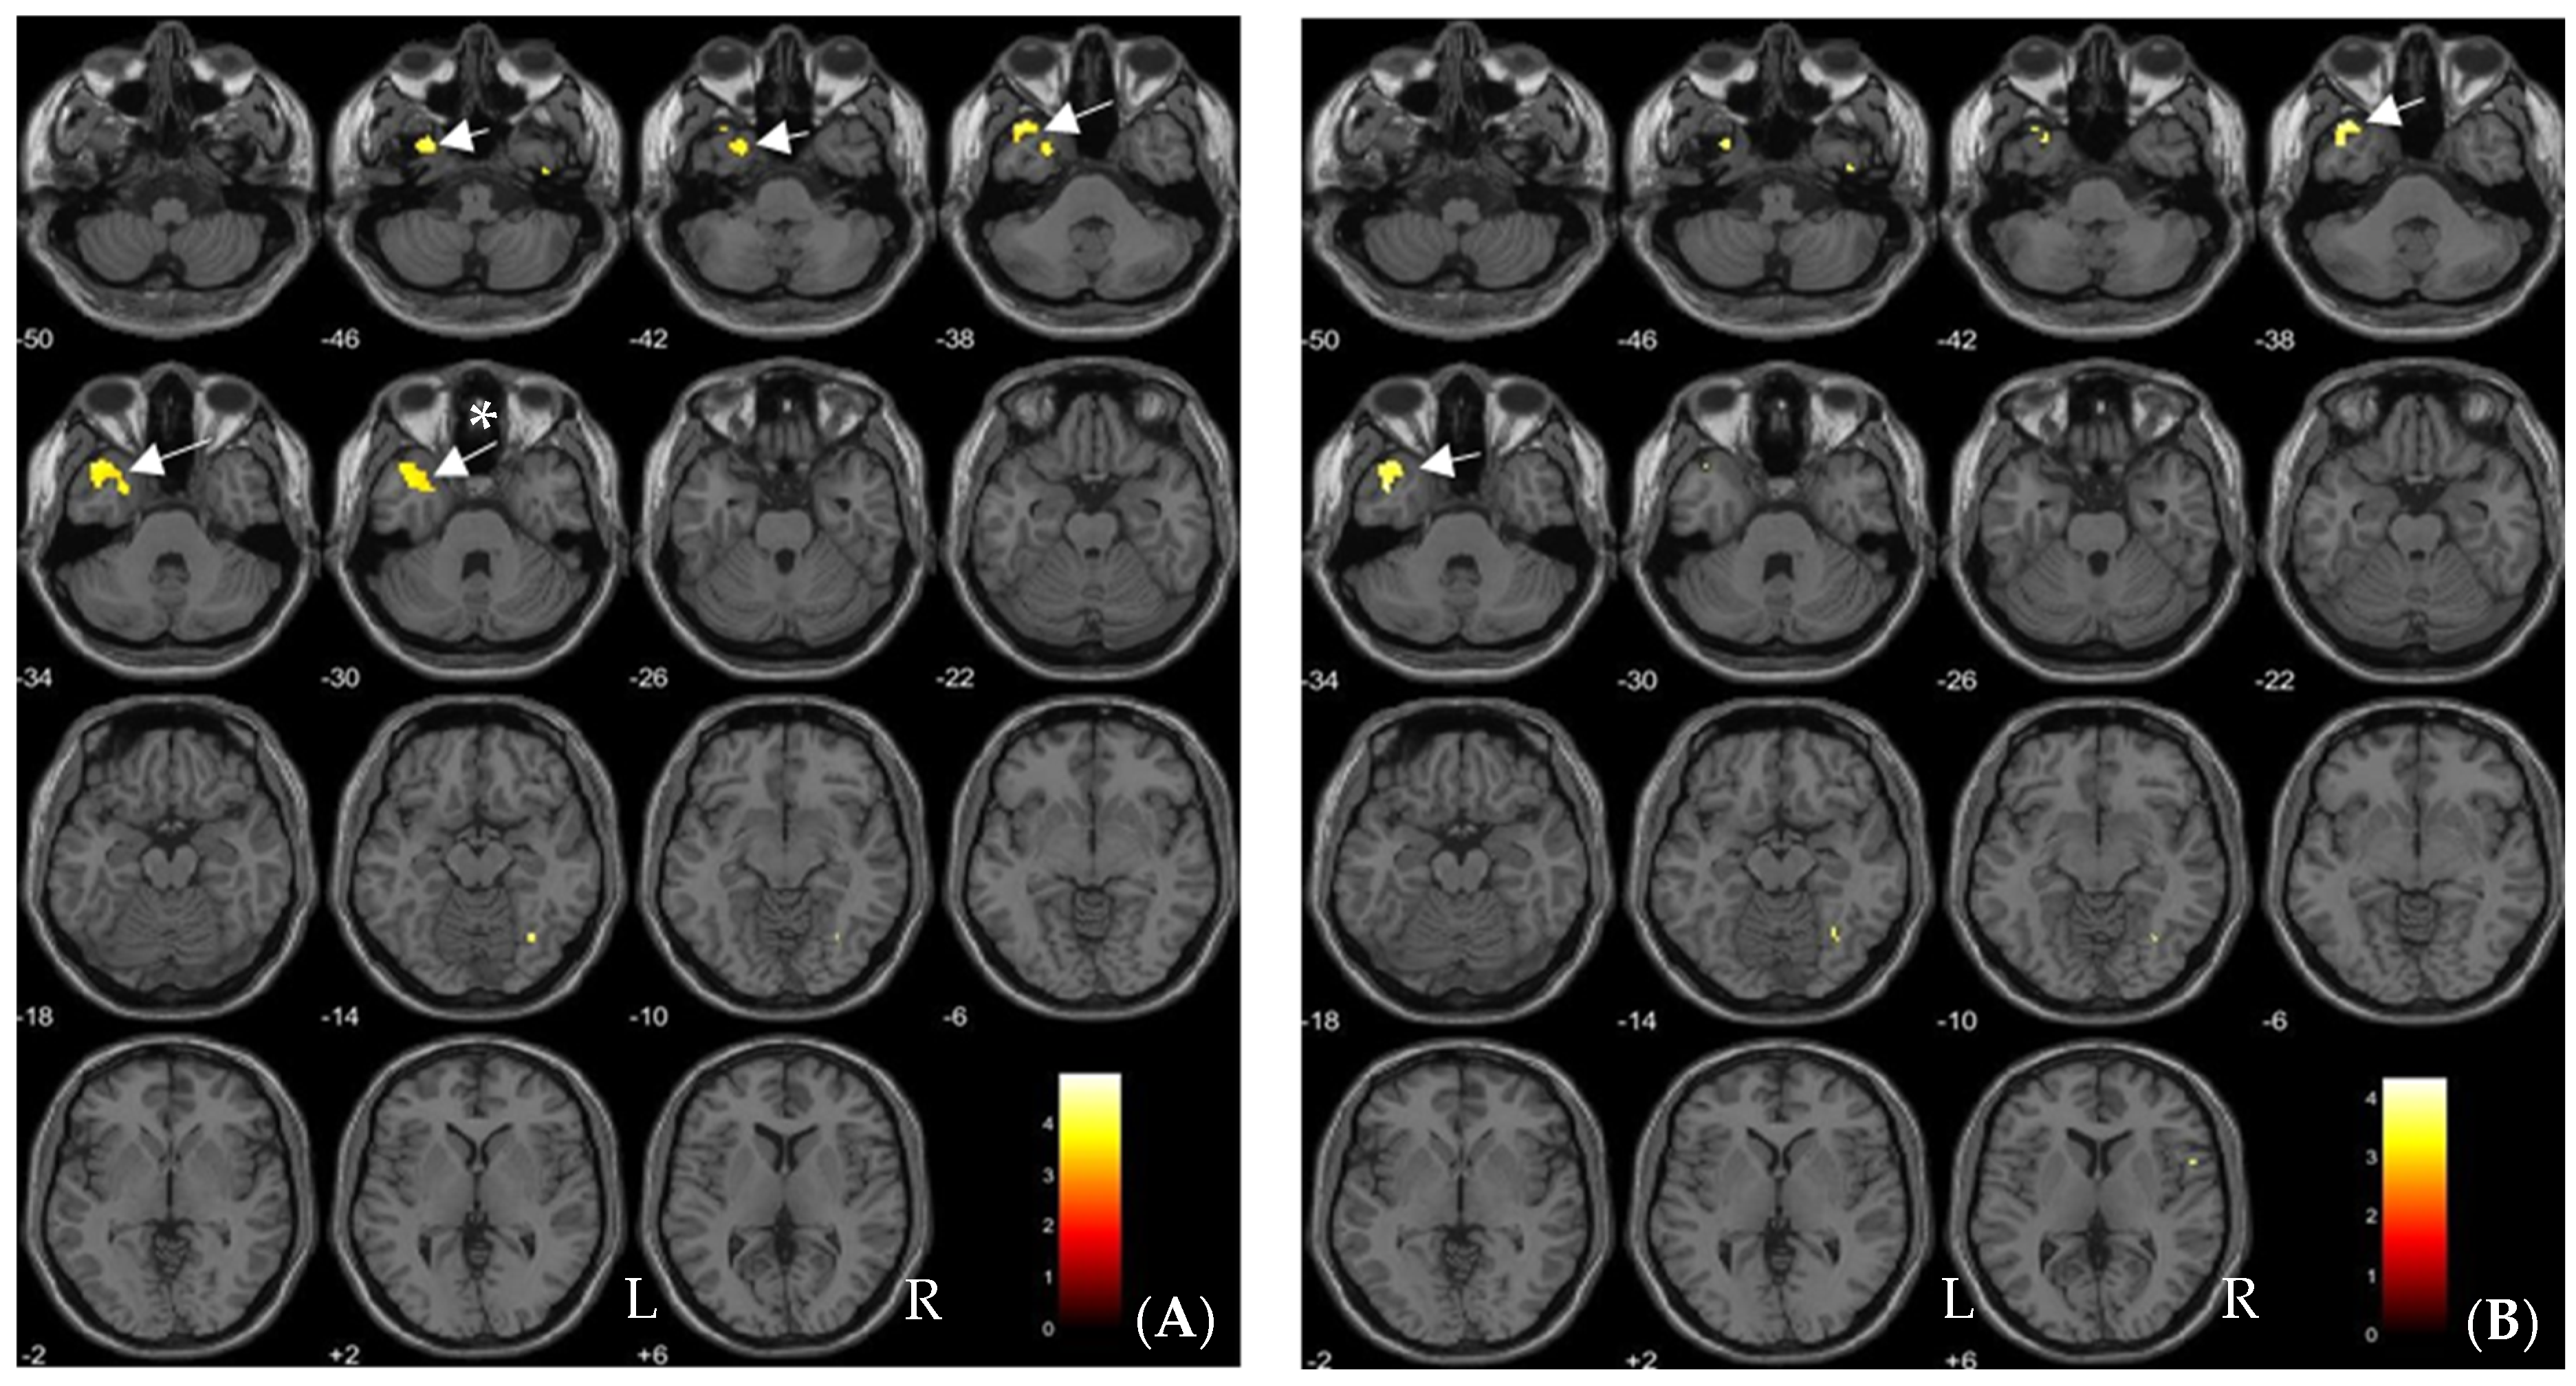

| Brain Regions | No of Voxels in Each Cluster (k) | Peak Z Scores | MNI Coordinates | ||

|---|---|---|---|---|---|

| x | y | z | |||

| Without exposure > With exposure | |||||

| Left inferior frontal gyrus pars orbitalis | 414 | 3.86 | −32 | 39 | −23 |

| With exposure > Without exposure | |||||

| No brain region | - | - | - | - | - |